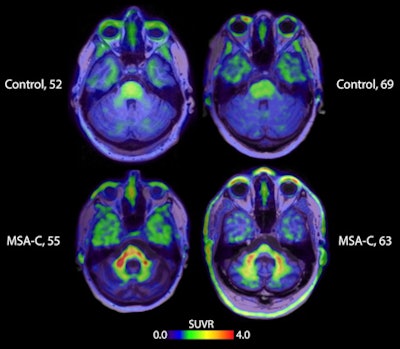

Brain scans taken with the tracer strongly indicate the signal specificity for alpha-synuclein in MSA patients, compared with healthy volunteers and patients with other alpha-synucleinopathies, like Parkinson's disease and Lew Body Dementia. The results represent the potential for earlier and more reliable differentiation for MSA, lead researcher, Dr. Oskar Hansson, PhD, of Lund University, said in a press release.

PET images using the radiotracer ACI-12589 (Selegiline, AC Immune) showing visual uptake in areas of interest associated with multiple system atrophy (MSA). Image courtesy of AC Immune.Furthermore, the tracer showed target engagement in vivo in alpha-synucleinopathies with a pharmacokinetic and safety profile suitable to be developed as a human brain PET imaging agent. Specifically, the ACI-12589 data showed enhanced contrast and alpha-synuclein target specificity in those with MSA. Tracer retention was highest in areas affected by MSA disease processes, particularly cerebellar white matter, according to the trial results.